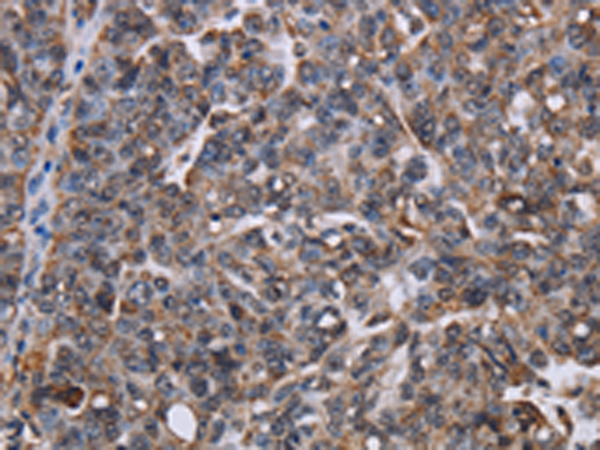

分类: 科研抗体货号: P08474别名: Mar7; BCUR1; Mart7应用: IHC反应种属: Human